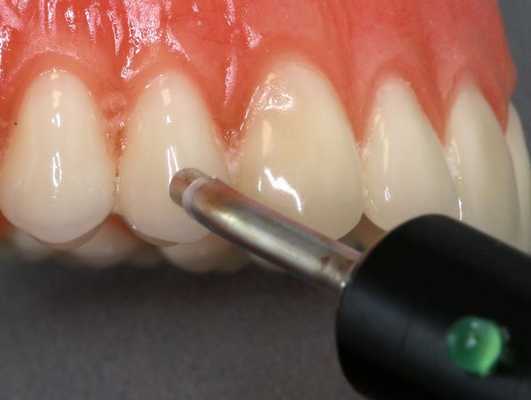

Диагностика периодонтита проводится на основании жалоб пациента, анамнеза заболевания, оценки общесоматического статуса, осмотра головы и шеи, полости рта, зуба, его перкуссии, зондирования и термопробы, электроодонтодиагностики (ЭОМ) и рентгенологического исследования. [10]

ЭОМ — это метод стоматологического исследования, основанный на определении порогового возбуждения болевых и тактильных рецепторов пульпы зуба при прохождении через неё электрического тока.